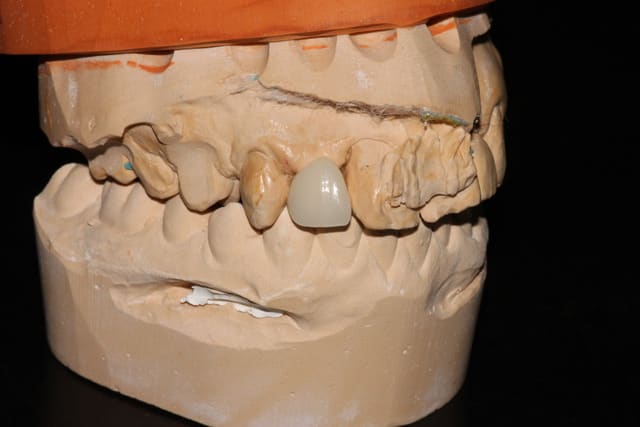

Bonjour, je viens d'avulser une 11 (Résorption externe+ perte d'attache terminale, j'avais tenté l'endo mais les douleurs persistaient), dont j'ai conservé la couronne que j'ai collé aux dents adjacentes dans un soucis esthétique.

-Bridge collé: c'est la meilleure solution à mon avis, d'autant plus que la patiente présente une belle classe 2 ce qui me permettrait un collage sur les incisives voire canines sans risque de sur-occlusion. Je n'ai cependant jamais fait ce genre de choses, pensez vous que çà soit réalisable? Avez vous des informations à me donner? Comment coter avec la CCAM? (j'ai cru comprendre que ce n'était pas possible)

Le bridge collé peut être une bonne solution de compromis: compromis technique, esthétique et financier.

Collage superbond pour le métal.

@ Seteph: effectivement, çà semble une très bonne solution, le cas est vraiment similaire à celui de tes photos. Par contre la préparation des dents est tout de même importante, non? Et du coup se posent mes questions sur la réalisation et cotation de ce type de bridge.

Ah oui... Et sans aucune préparation si ce qui te fait peur...et ça rassurera ta patiente...( il faut 1 mm d épaisseur , pas moins... Donc idéal si présence dune classe 2.

Je suis parti sur le bridge collé composite de canine a canine. Je vous dirait ce que çà donne. J'ai également parlé de l'implant à terme qui pourrait se tenter aussi.